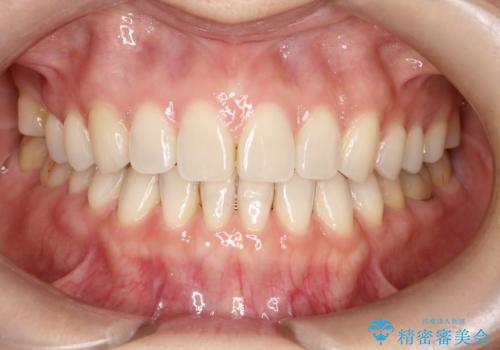

【インビザラインで再矯正】マウスピース矯正で隙間を閉じたい

- 過去に矯正を行ったあと、前歯の後戻りを主訴に来院されました。

マウスピース矯正にて隙間を閉じる計画をたて、治療を行いました。